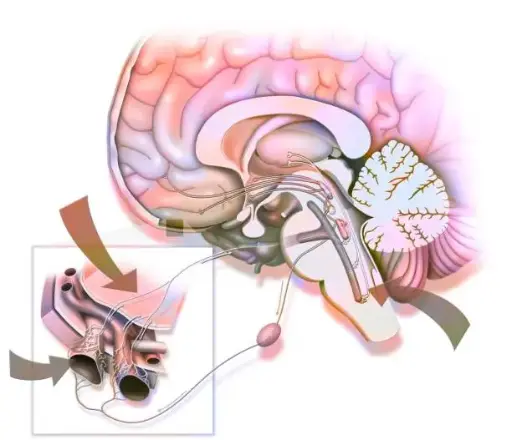

This course provides a focused and in-depth exploration of glossopharyngeal neuralgia (GPN), a rare but debilitating cranial nerve disorder. Covering the anatomical and physiological basis of cranial nerve IX, it delves into the underlying pathophysiological mechanisms, distinctive clinical features, diagnostic approaches, and advanced treatment strategies. Emphasis is placed on evidence-based medical therapies and the latest surgical interventions, including microvascular decompression and radiosurgical techniques. Designed for clinicians and medical students, this course equips learners with the knowledge needed to accurately diagnose and manage GPN in both routine and complex clinical scenarios.